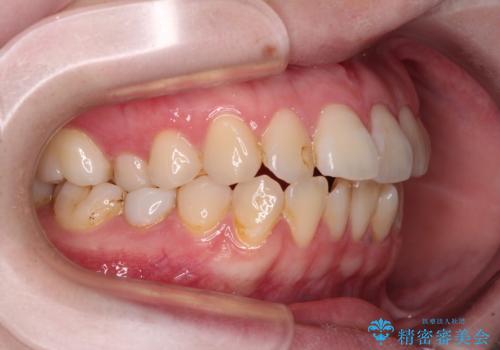

開咬と前方に飛び出した前歯 インビザラインによる矯正治療

- 上下前歯の非接触と叢生を気にして来院された患者様です。

開咬の改善はインビザラインの最も得意とするところであるため、インビザラインを用いて矯正治療を行うこととしました。

舌の突出癖改善のトレーニングをしっかりと行っていただき、上下前歯が接触する咬み合わせを達成することができました。